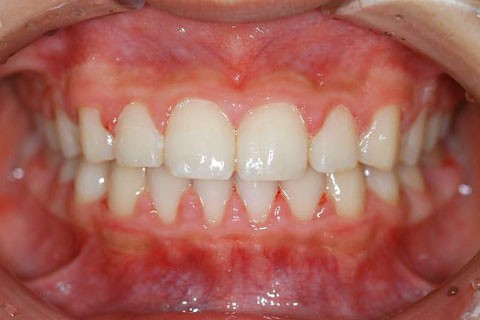

矯正の症例 受け口(反対咬合)

受け口(反対咬合)の症状

下あごが上あごより突出しているか、上あごが下あごより後退している状態で、咬み合わせが逆になっているので反対咬合ともいいます。お子様の場合、受け口(反対咬合)を放置していると、成長期において下あごが過大に成長し悪化しますので、出来る限り早い時期に治療することをおすすめします。受け口(反対咬合)は見た目の問題だけでなく顎の動きを制限し、将来的に顎の痛み(顎関節症)を引き起こす場合があります。また、お子様の場合は、正常な上顎の成長を阻害する可能性があります。